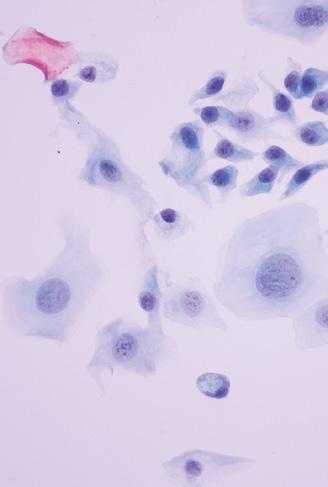

Η θεραπεία με CAR-T

απομονώνοντας τα Τ-λεμφοκύτταρα. Στη

συνέχεια, αυτά τα κύτταρα μεταφέρονται με ασφάλεια σε ένα εξειδικευμένο κέντρο παρασκευής, όπου τροποποιούνται σε CAR-T κύτταρα, που μπορούν να αναγνωρίσουν έναν συγκεκριμένο στόχο. Στους ασθενείς χορηγούνται χαμηλές δό-

κύκλου, ενισχύοντας την ανοσιακή α-

απάντηση